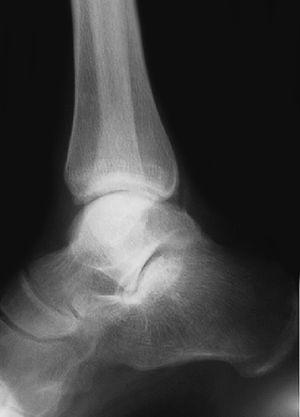

Respecto a las luxaciones del astrágalo, se han encontrado 7 casos de las cuales 5 (71,4%) de ellas eran luxaciones mediales --el pié se desplaza hacia adentro con respecto al astrágalo-- (figs. 13 y 14). La luxación medial es la más frecuentes --el 72% del total según DeLee y Curtis30 y Zimmer y Johnson31, y el 85% para Motley et al6--, seguidas de las laterales (de peor pronóstico) y mas infrecuentes las anteroposteriores.

Fig. 13. --Enucleación del astrágalo. Reducción, desbridamiento y estabilización temporal con agujas K.

Fig. 13. --Enucleation of the astragalus. Reduction, debridement and temporary stabilisation with Kirschner needles.

Fig. 14. --A) Radiografía al sexto mes: osteoporosis. B) Radiografía a los 18 meses: artrosis tibioastragalina.

Fig. 14. --a. Radiography at 6 months. b. Radiography at 18 months: tibio-astragalar arthrosis.